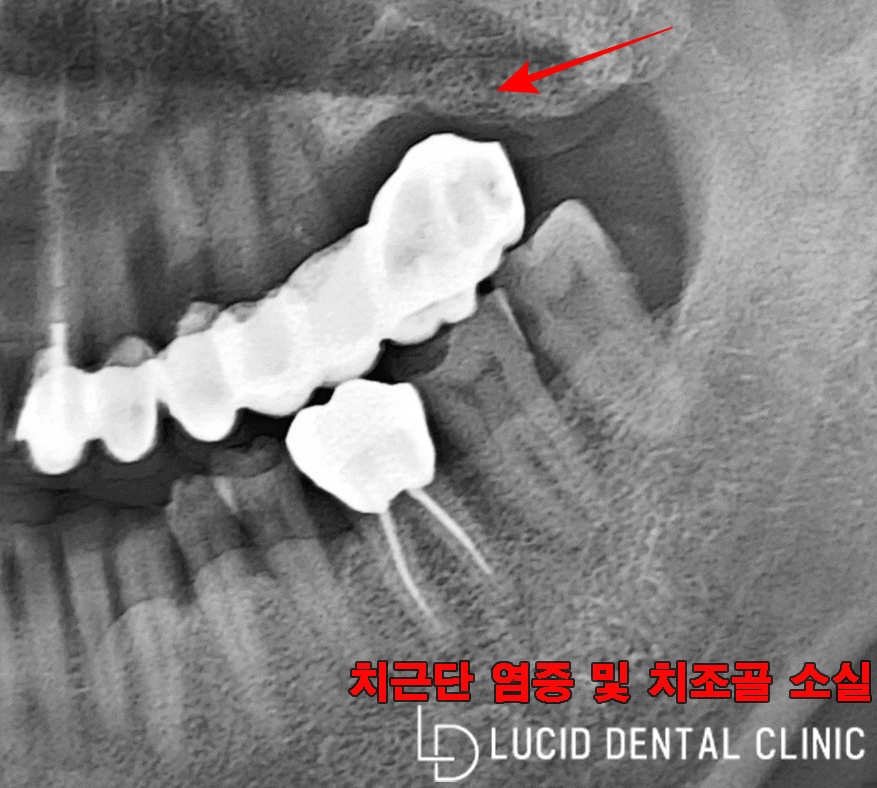

더 놀라운 건, 오른쪽 구강이었는데요

이미 다수의 브릿지 보철치료를 받았으나

캔틸레버 브릿지로 한쪽 지지대가 없었고,

치근단 염증이 심하게 진행되며 함께

치조골 퇴행이 일어난 걸 발견했습니다.

이대로라면 브릿지가

제대로 고정되지 않아

저작 기능을 포함한 모든 일상

생활에 큰 불편이 있었을 텐데요

계속 방치하다간 더 큰

질환으로 이어질 수 있어